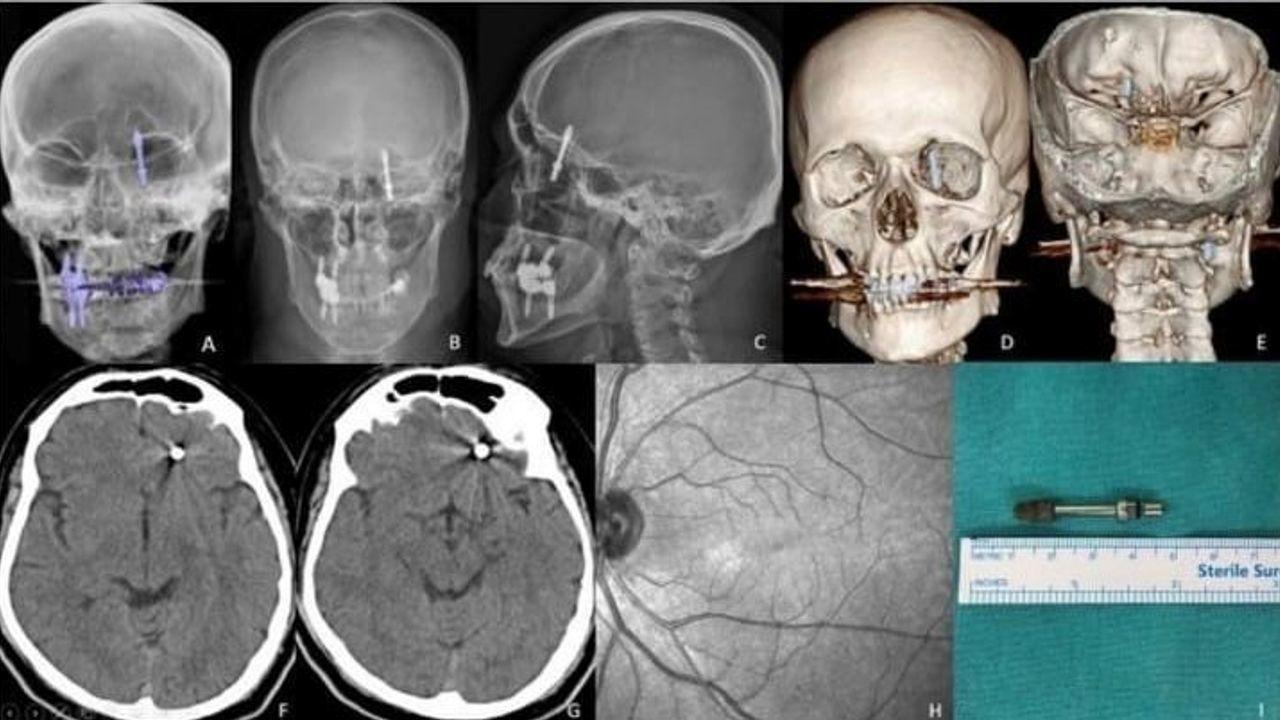

BURSA (İHA) – Bursa’da Diş tedavisi için gittiği özel klinikte yaptırdığı implant süreci, fabrika çalışanı Ramazan Yılmaz’ın (40) hayatını kabusa çevirdi. Argümana nazaran, tabibin kusurlu müdahalesi sonucu implant vidası çene kemiğini delip kafatasına saplandı. Vefatla burun buruna gelen şanssız adam, saatler süren ameliyatla hayata tutundu. Lakin ortadan geçen 2 yıla karşın ne adalet yerini buldu, ne de sorumlular cezalandırıldı. Yanlışlı bulunan diş tabibine ise yalnızca 10 muayene fiyatı Ceza verildi.Nilüfer ilçesinde özel Bir diş kliniğinde muayene olan Yılmaz’a, dişlerinin sallandığı gerekçesiyle implant tedavisi önerildi. Lakin teze nazaran, doktor A.D.’nin hatalı müdahalesi sonucu implant vidası çene kemiğini delip kafatasına saplandı.Baygınlık geçiren Yılmaz, kliniğin kendi aracıyla hastaneye kaldırıldı. Tomografi çekiminde vidanın beynine kadar ilerlediği ortaya çıktı. Acil ameliyata alınan şanssız adam, saatler süren operasyonla mevtten döndü."İki yıldır mahkeme tarihi bile verilmedi"Olayın akabinde büyük bir travma yaşayan Ramazan Yılmaz, hem sıhhatini hem işini kaybetti. Tabipten ödediği fiyatın iadesini isteyen Yılmaz, ret yanıtı alınca hukuk çabası başlattı. Lakin iki yıldır evrakında tek bir duruşma günü bile verilmedi.Adli tıp raporunun evraka eklenmediğini söyleyen Yılmaz, "Beynime implant saplandı lakin kimse sorumluluk almıyor. Başhekime kadar gittim, hâlâ bir muhatap bulamadım" diyerek yaşadığı çaresizliği anlattı.Diş doktoruna yalnızca 10 muayene fiyatı cezasıBursa Diş Tabipleri Odası, olayla ilgili doktor A.D.’ye yalnızca 10 muayene fiyatı meblağında para cezası verdi. Bu kararı "insan hayatını hiçe saymak" olarak nitelendiren Yılmaz, "İnsan hayatı 5 bin lira mı?" kelamlarıyla reaksiyon gösterdi.Birliğe de dava açtığını belirten Yılmaz, "Adaletin tecelli etmesini bekliyorum. Raporlar bir biçimde engelleniyor. İnsan hayatına mal olacak bir yanlışa imza atıldı, lakin kimse hesap vermiyor." dedi."Kamu vicdanı bu kararı bekliyor"Sağlık Bakanlığı ve adli makamların sessizliğinden keder yanan Yılmaz, "İki yıldır bekliyorum. Adaletin yerini bulmasını, sorumluların cezalandırılmasını istiyorum. Bu yalnızca benim değil, tüm toplumun problemi. Bu türlü kusurlar cezasız kalmamalı" diyerek davette bulundu.